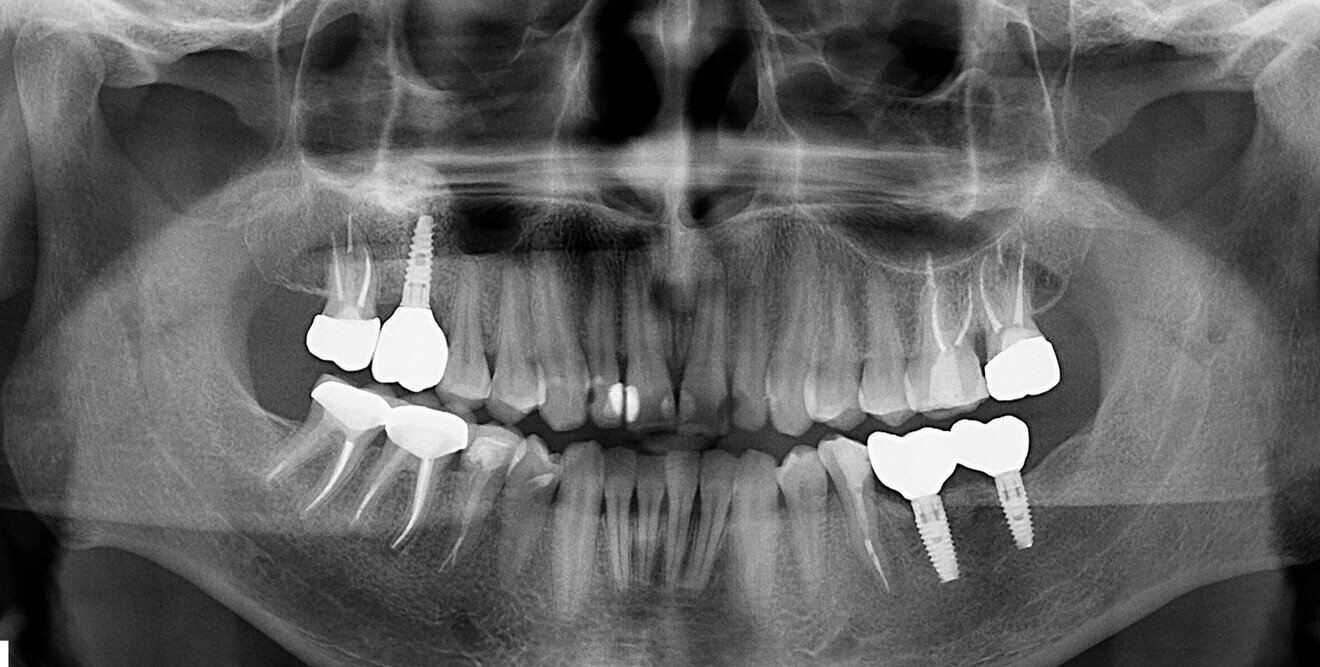

Fig. 20 : Radiographies prises en 2017.

Fig. 21 : Radiographie prise  en 2019.

Fig. 22 : Radiographie  prise  en 2022.